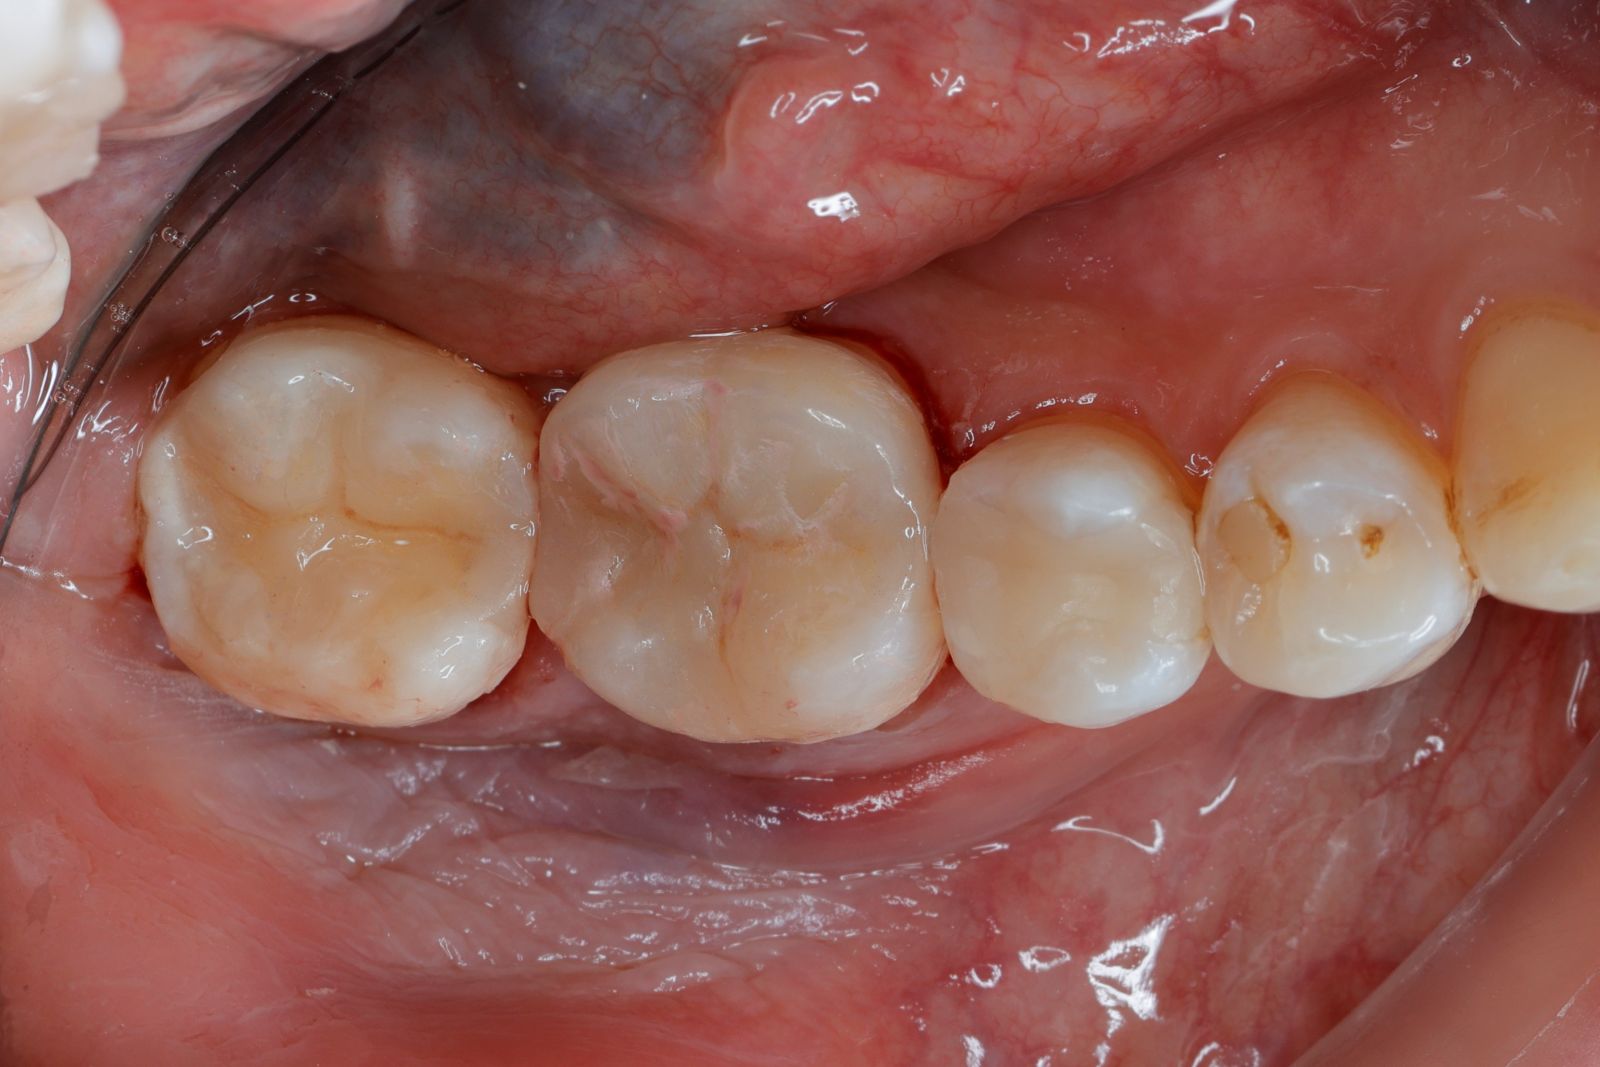

【 案 例 二 】